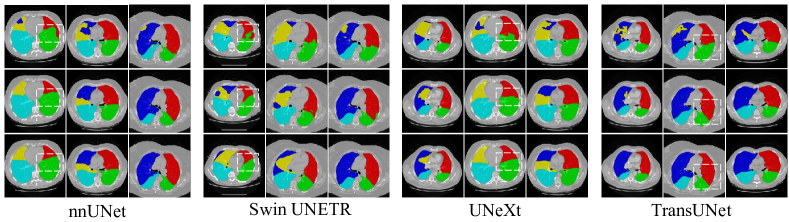

4.4.5 Ablation on plug-and-play Characteristics of the pull-push mechanism

Similarly, we also investigate the plug-and-play Characteristics of pulling and pushing branches. As shown in Table 8, baseline models incorporated with these two branches can achieve better performance on the fused lung lobe dataset, which reveals that the pull-push mechanism bears excellent plug-and-play properties. Specifically, the pull-push mechanism brings significant performance increases for TransUNet and UNeXt, with and Dice increases respectively. More detailedly, the segmentation task on the right lobes can be better solved, which means that pushing and pulling branches are competent to address boundary confusion. Further, we carry out qualitative analysis on the effectiveness of the pull-push mechanism when plugged into other segmentation models. As shown in Figure 13, we select nnUNet [1], Swin UNETR [57], UNeXt [58] from the family of CNNs, Transformer-based and MLP-based models respectively as baseline models. The introduction of SDM and CCM will promote the segmentation precision of inter-class boundary regions, especially in the right lobe.